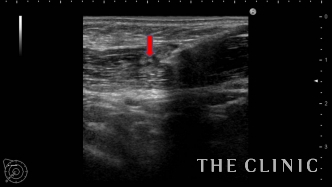

画像は、しこりの中に注射針を穿刺したところと、ヒアルロニダーゼを注入しているところです。

ヒアルロニダーゼが入ると加水分解して白く点状の画像として描出されます。

しこり全体にヒアルロニダーゼが浸透するように十分な量を注入することがポイントです。